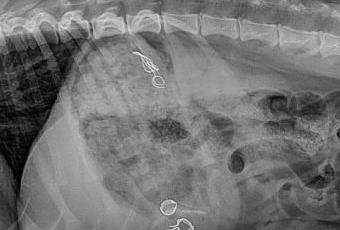

... Le Bull-Terrier est carnivore comme tous les chiens. Le Bull-Terrier est omnivore comme nous. Le Bull-Terrier est aussi frutivore, le Bull-Terrier est Playmobilivore, Numismativore, ParisMatchivore et récemment CouronnedefleursBalinaisivore. Alors les fleurs en papier, pas de problème, ça passe tout seul, le bois, ça se chique facilement et ça se décompose lentement mais les petites pièces en acier qui retiennent tout le bordel, ça passe moins bien. Enfin, ça passera. D'ici deux jours. D'un autre côté, on n'a pas tous les jours l'occasion de voir son chien de l'intérieur et Ekta, je dois te dire que tu es très jolie du dedans aussi. Voilà, c'est dit.